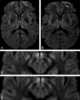

Diploic channel

The diploic veins are large, thin-walled valveless veins that channel in the diploĆ« between the inner and outer layers of the cortical bone in the skull. They are lined by a single layer of endothelium supported by elastic tissue. [Source: Wikipedia ]